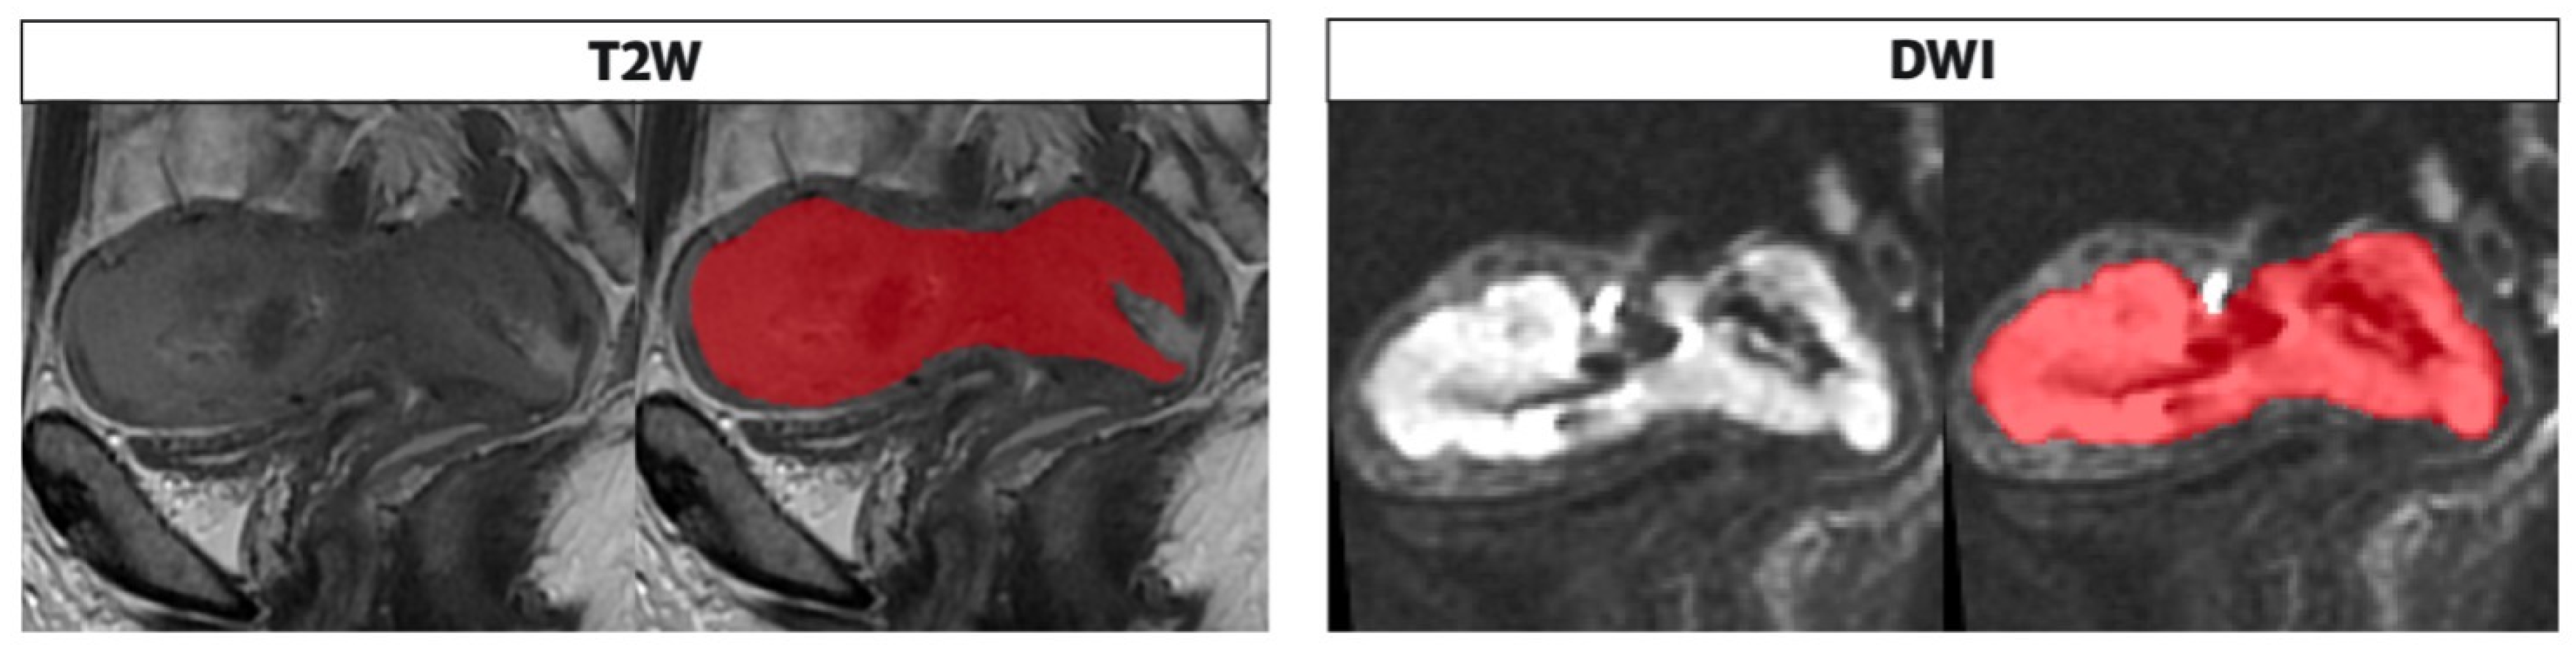

The whole tumor segmentations were performed by a radiologist (V.C.) with 4 years of expertise in gynecological imaging who manually outlined the region of interest (ROI) on the T2WI and DWI along tumor boundary on each slice; the segmentation was subsequently reviewed by senior radiologist with 25 years experience in pelvic female tumors (L.M.) (Figure 3). The radiologists were blind to the clinical and pathologic outcomes. The segmented tumor area appeared as intermediate/low intensity compared to the normal myometrium for T2WI, while it appeared as high intensity for DWI.

Figure 3. Segmentation performed on T2 and DWI sequences in the sagittal plane along the tumor boundary. The endometrial cavity is replaced by solid heteroplastic tissue characterized by intermediate signal intensity in the T2 sequences and high signal compared with the neighboring myometrium in the DWI images; the tumor is bounded by the red area as shown in the figure alongside both sequences as performed in the segmentation process, on the T2 and DWI.